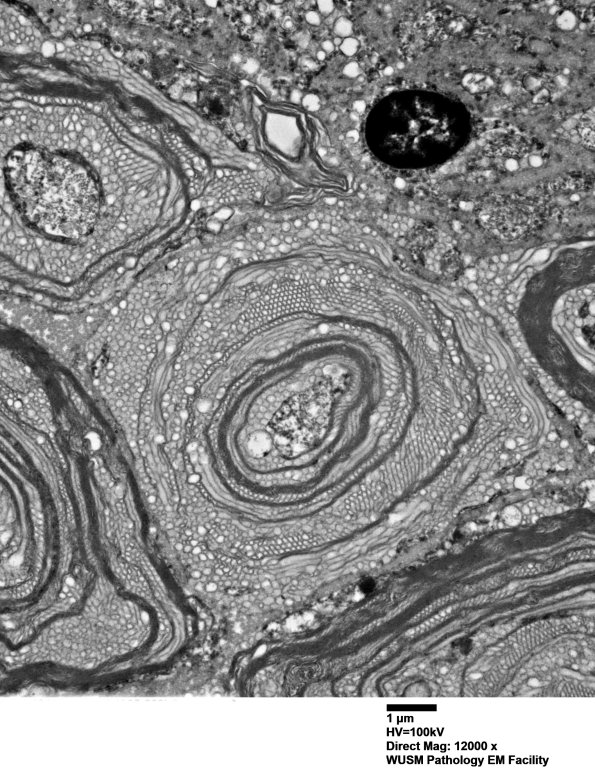

20E4,5 Two magnifications of an axon undergoing vesicular myelin change and axonal degradation. (electron micrographs)